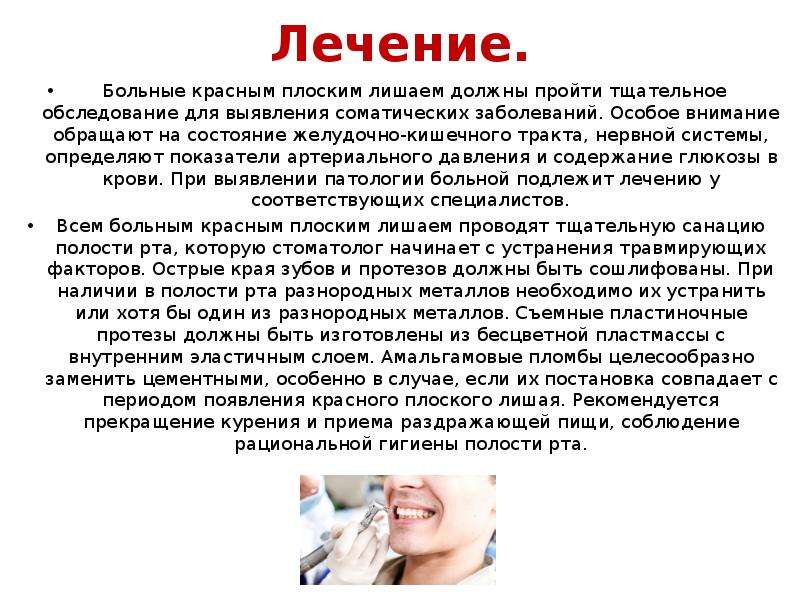

Фото Красного Плоского

Фото Красного Плоского 103 фото